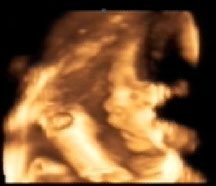

19.05.2010 - kontrola v 32+3tt- velký UTZ, jsme hlavičkou dolů, váha odhad 2.063g, CS 0, kontrola za 4 týdny

16.06.2010- kontrola v 36+3tt- pásy ok., malá má 2700g, hlavičkou dolů. zatím se prý nechystá, jsem chudokrevná, kontrola za týden